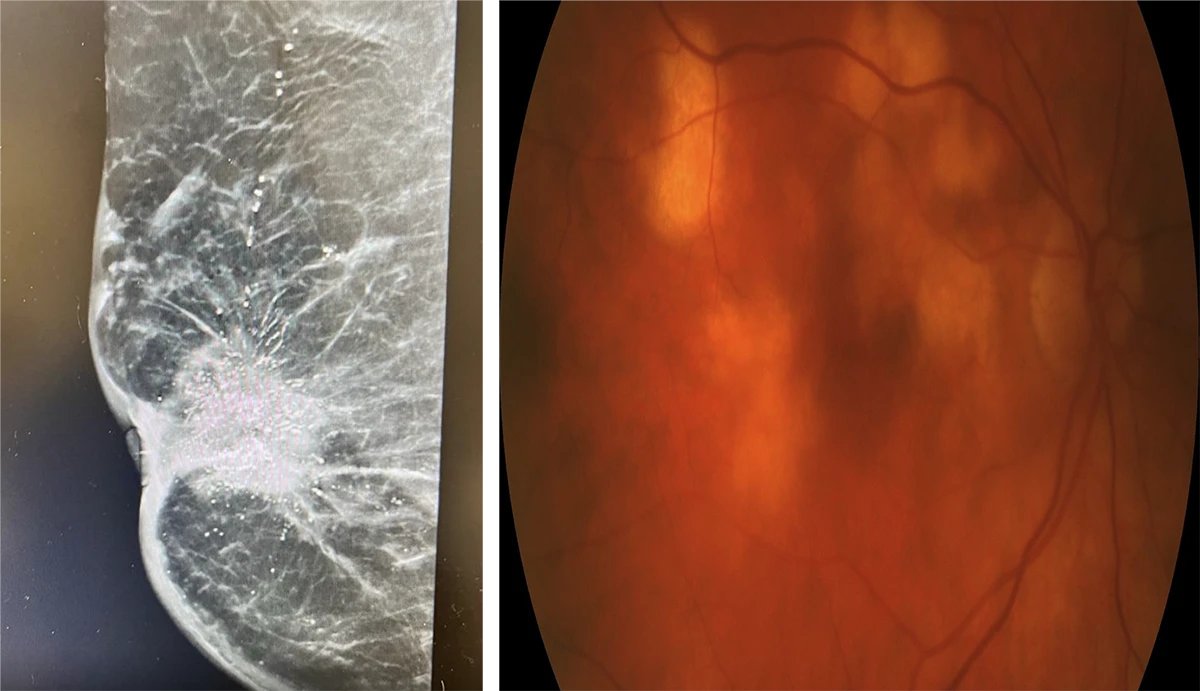

A 64-year-old woman presents with slightly reduced vision in the right eye.

She described “feeling sick” for the last 4 weeks. No significant ocular or medical history was reported.

VA 6/18 OD, 6/6 OS

Answer D

- Mean diameter 9.5mm with thickness of 3.2mm

- Most commonly yellow in colour

- Breast most common site for primary in females